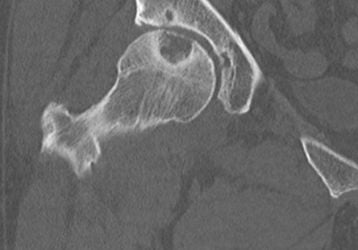

• Дисплазия. Для болезни характерно неправильное развитие сочленения. При нем головка кости бедра выпадает из вертлужной впадины.